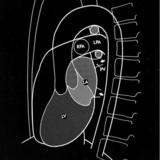

Rt heart

Date: 03/11/2006

Views: 3202